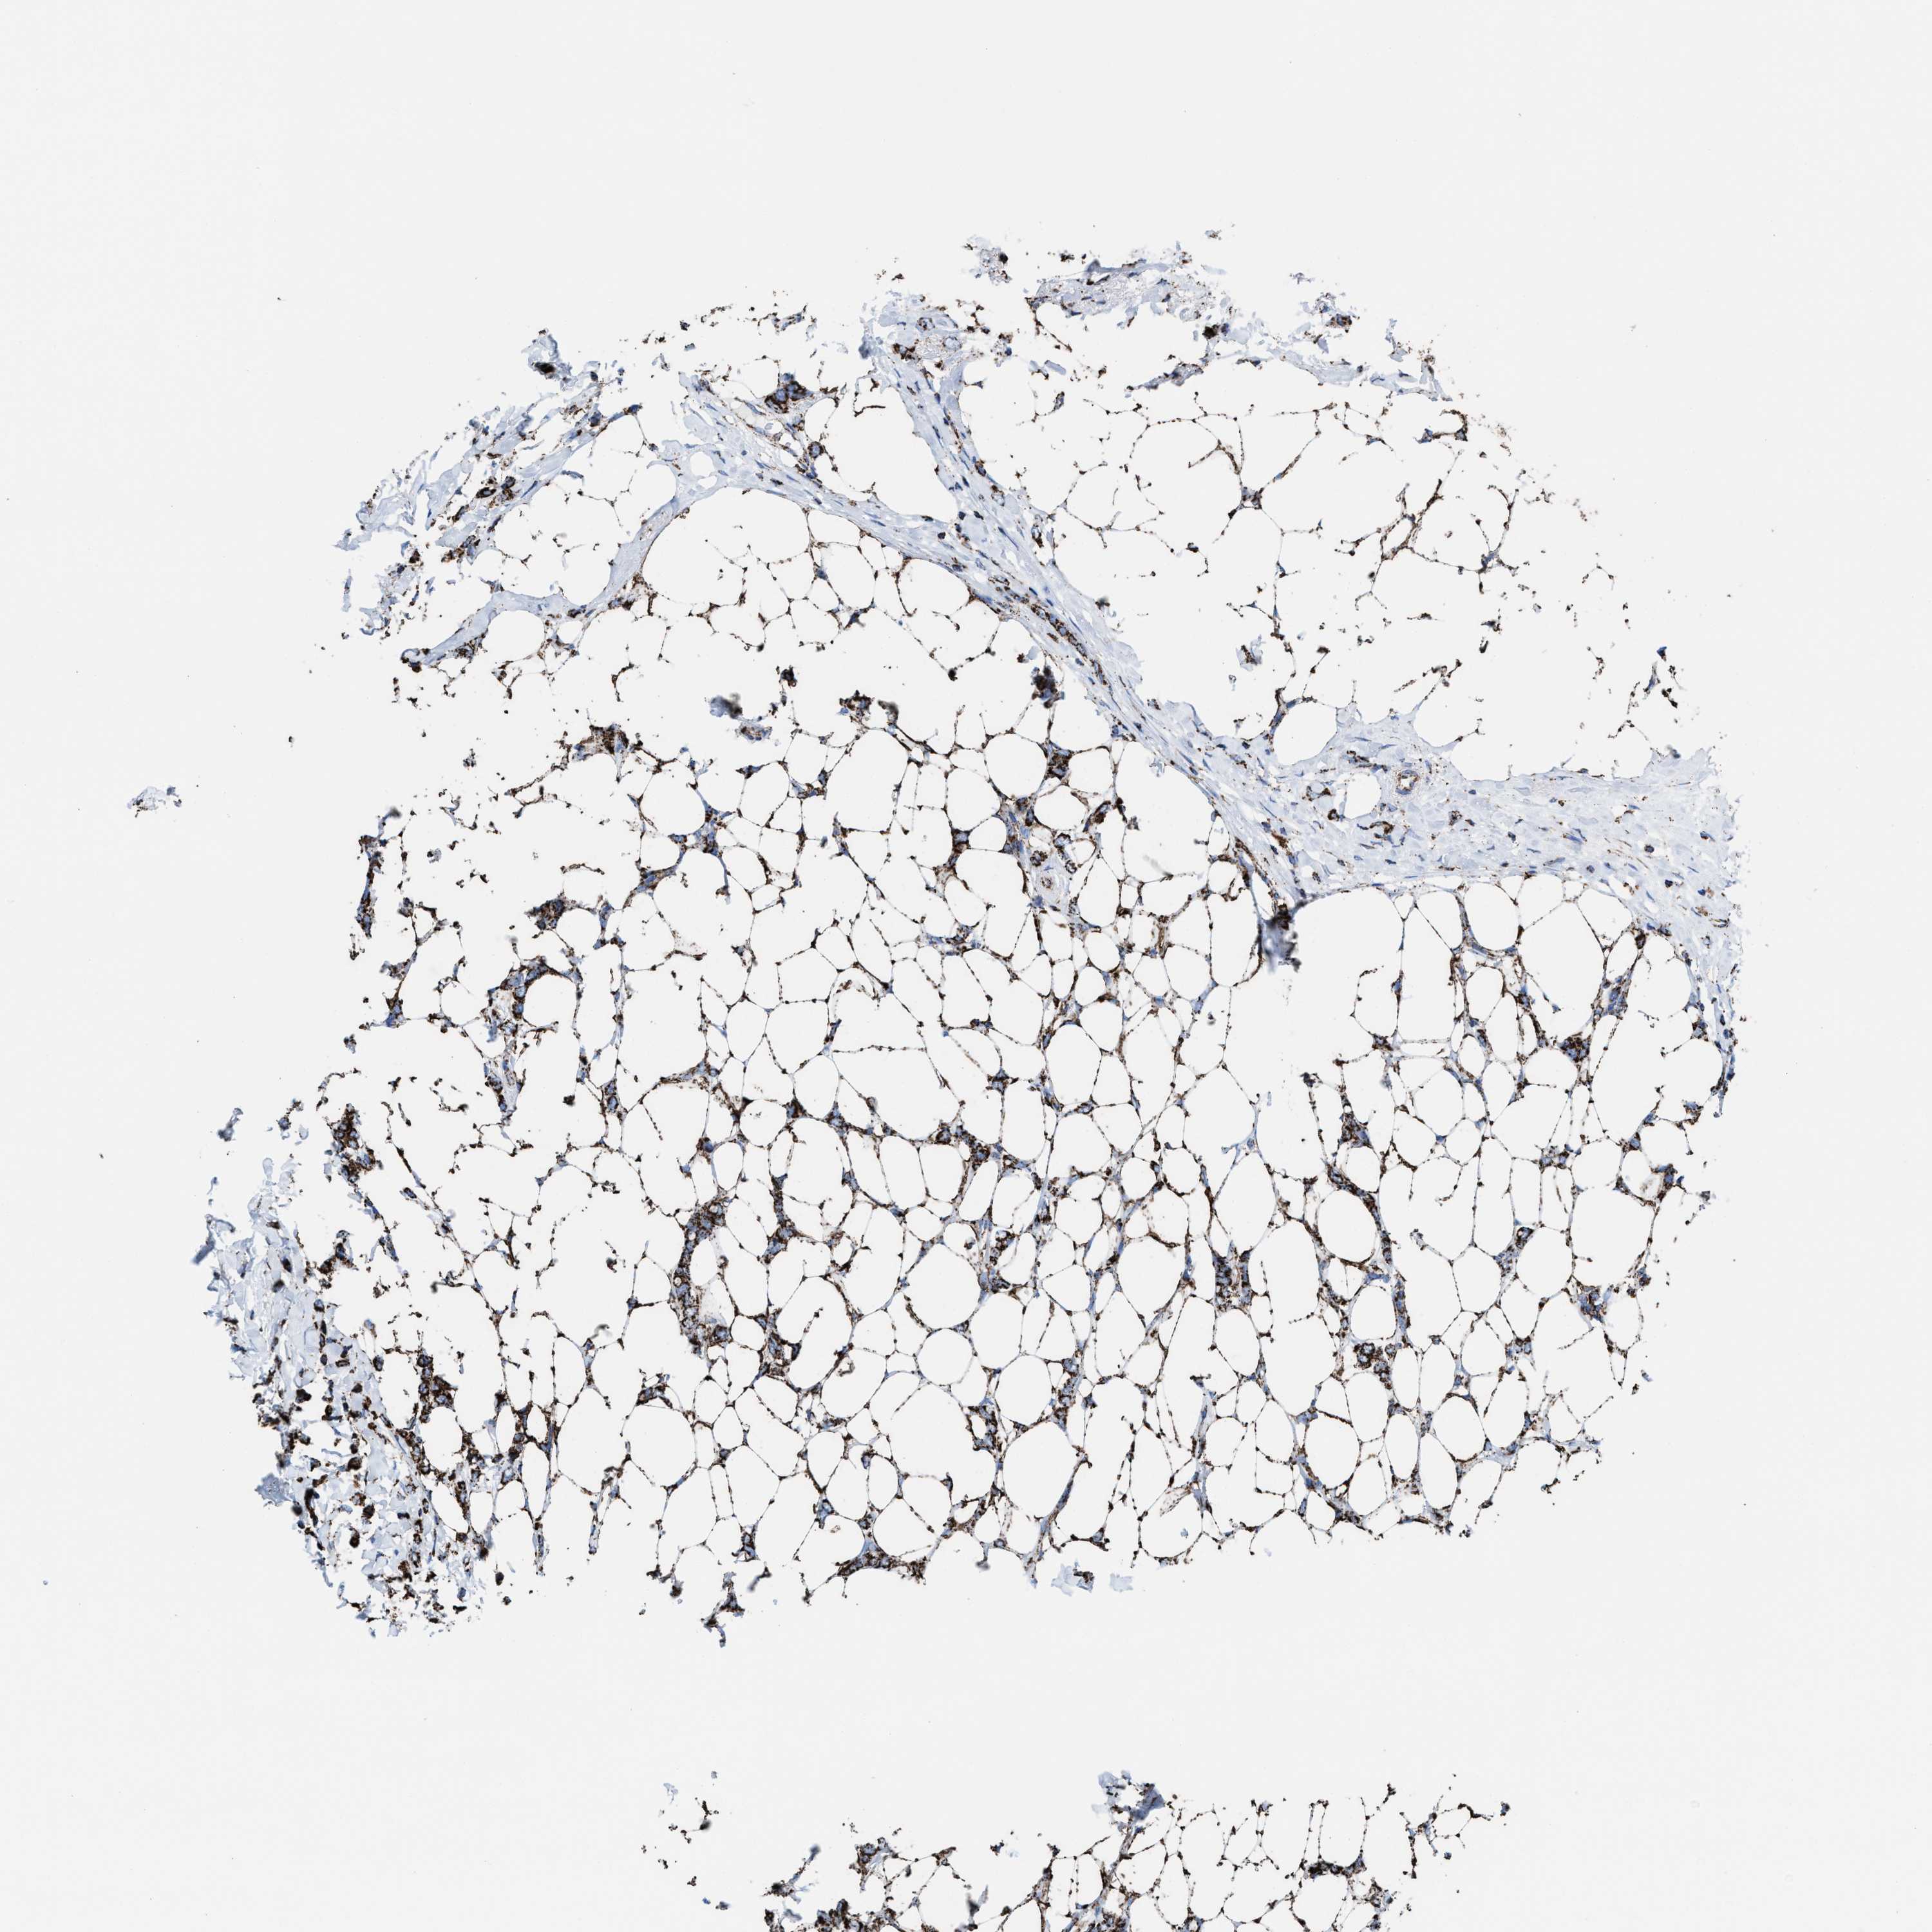

CANCER BREAST CANCER Show tissue menu

BRCA TCGA BRCA VALIDATION PROTEIN EXPRESSION

ANTIBODIES

AND

VALIDATION